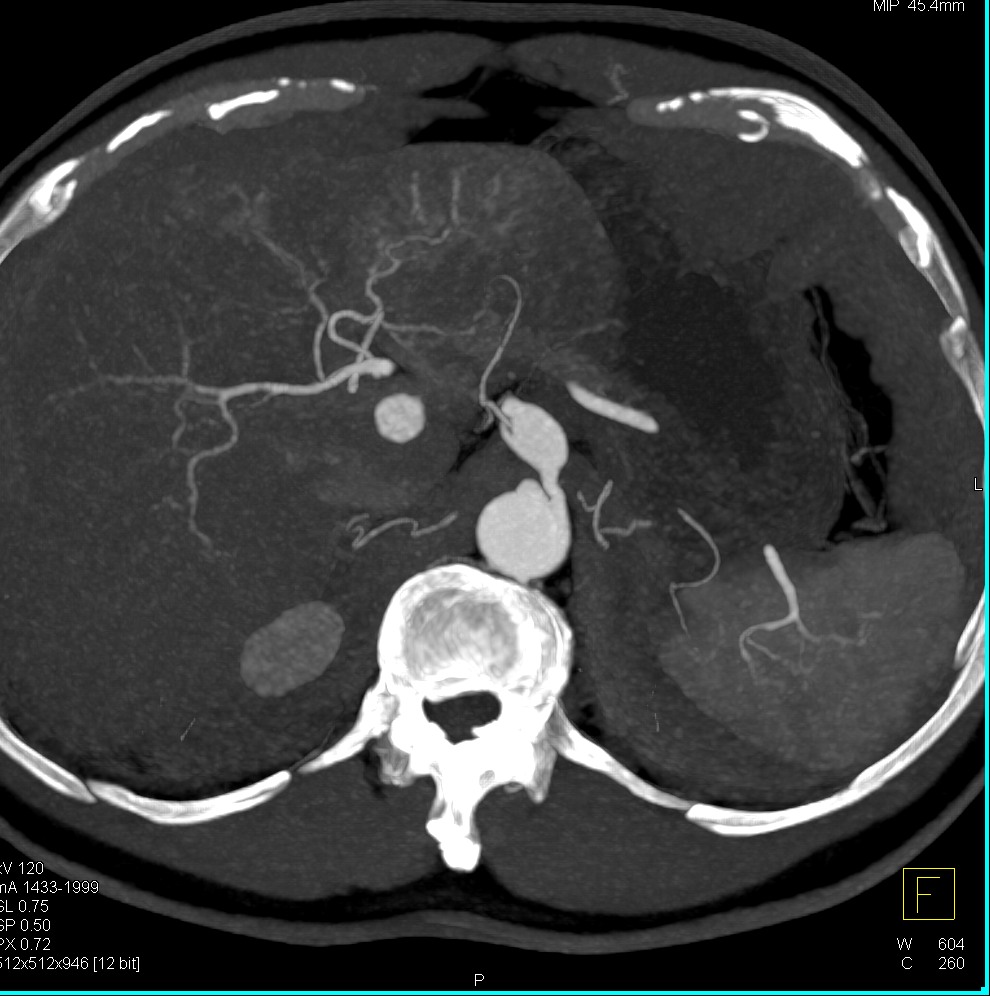

@ctisus

Elliot K Fishman / CTisus.com

12 hours

Hepatic Artery Aneurysm